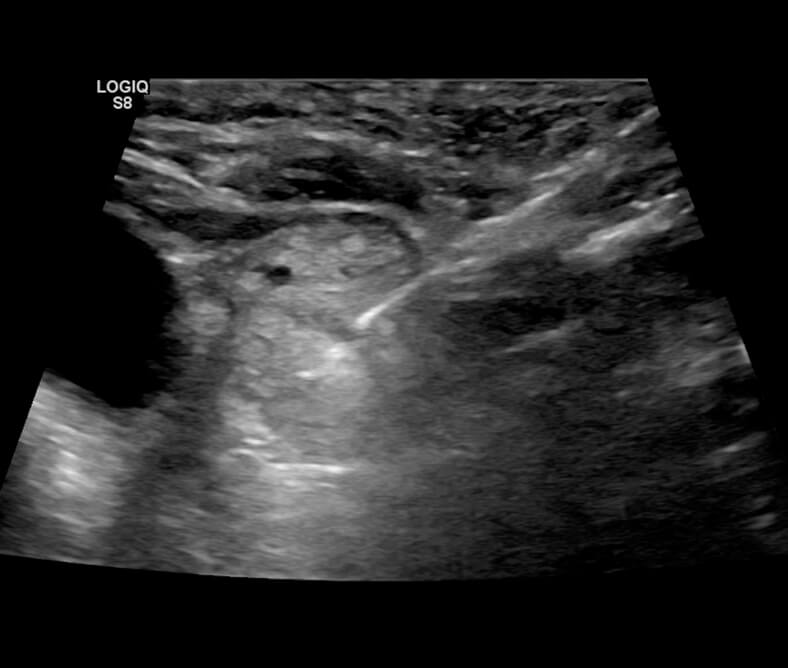

Θερμοκαυτηρίαση με ραδιοσυχνότητες στον θυρεοειδή

Μια πρωτοποριακή μέθοδος για την αντιμετώπιση των καλοήθων όζων του θυρεοειδή είναι η χρήση των ραδιοσυχνοτήτων (RF ablation). Γίνεται στο Μetropolitan Hospital, με τοπική αναισθησία, χωρίς τομές και οι ασθενείς εξέρχονται την ίδια μέρα.

Η ένδειξη για την αντιμετώπιση των όζων με αυτή την μέθοδο τίθεται σε συνεννόηση με τον θεράποντα ενδοκρινολόγο. Η έως τώρα εφαρμογή αυτής της μεθόδου παγκοσμίως, γίνεται σε τεκμηριωμένα καλοήθεις όζους θυρεοειδούς, όταν υπάρχει αντένδειξη για χειρουργική εξαίρεση ή όταν ο ασθενής δεν επιθυμεί την αφαίρεση του αδένα.

Εφαρμόζουμε επίσης, την νέα αυτή μέθοδο σε ασθενείς με υποτροπή στην χειρουργική κοίτη ή σε τραχηλικό λεμφαδένα, στις περιπτώσεις που δεν είναι εφικτή η επανεπέμβαση.